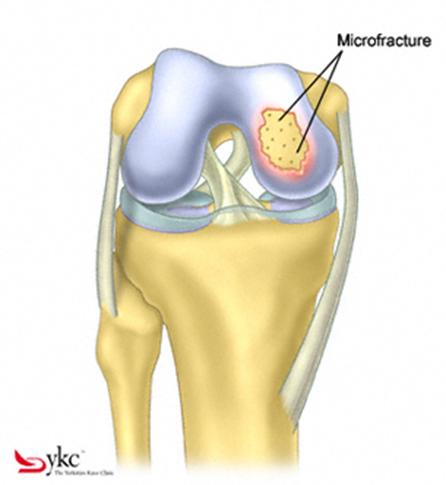

Dupa indepartarea cu succes a stratului de cartilaj calcifiat, o andrea este folosita pentru a face mai multe gauri mici (mirofracturi) in osul expus al defectului condral aflate la distanta de 1-2 mm. Trebuie lasata o punte de oase potrivita intre gauri. Tehnica de microfracturi are numeroase avantaje fata de foraj. Mai intai de toate, creaza o leziune termala mai mica. Mai mult, cu microfracturi chirurgul este capabil sa intre in zonele dificile ale suprafetei articulare cu un control mai bun asupra adancimii de patrundere. La finalizarea microfracturii, o suprafata aspra este generata pentru aderenta cheagului de sange care contine celule mezenchimale nediferentiate de la osul subcondral. Trebuie avut grija ca cele mai marginase parti ale leziuni sa fie patrunse de andrea pentru a ajuta la vindecarea tesutului reparator la imprejmuirea suprafetei articulare. Odata ce microfractura este finalizata, pompa artroscopica este oprita pentru a se asigura ca sangerarea maduvei curge din gaurile mici umpland defectul.[54]

Fig.21. Diagrama unei leziuni cartilaginoase.

Fig.23. Diagrama microfracturi: a. Leziunea; b. Rezultatul interventiei.